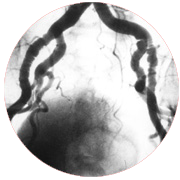

Coronary Angiography is a test that uses dye and special X-rays to show the interiors of your coronary arteries. To get the dye into your coronary arteries, your doctor will use a process called cardiac catheterization. A thin, flexible tube called a catheter is placed into a blood vessel in your arm, groin (upper thigh), or neck. The tube is eased into your coronary arteries, and the dye is released into your blood. Special X-rays are in use while the dye is flowing through the coronary arteries. These X-rays are called angiograms. The dye helps doctor study blood flow through the heart and blood vessels. This helps your doctor find blockages that can cause a heart attack.

An aortogram is an angiogram of the aorta. The aorta is the chief artery that conveys blood from your heart to your body. An aortogram may show the place and size of an aortic aneurysm.